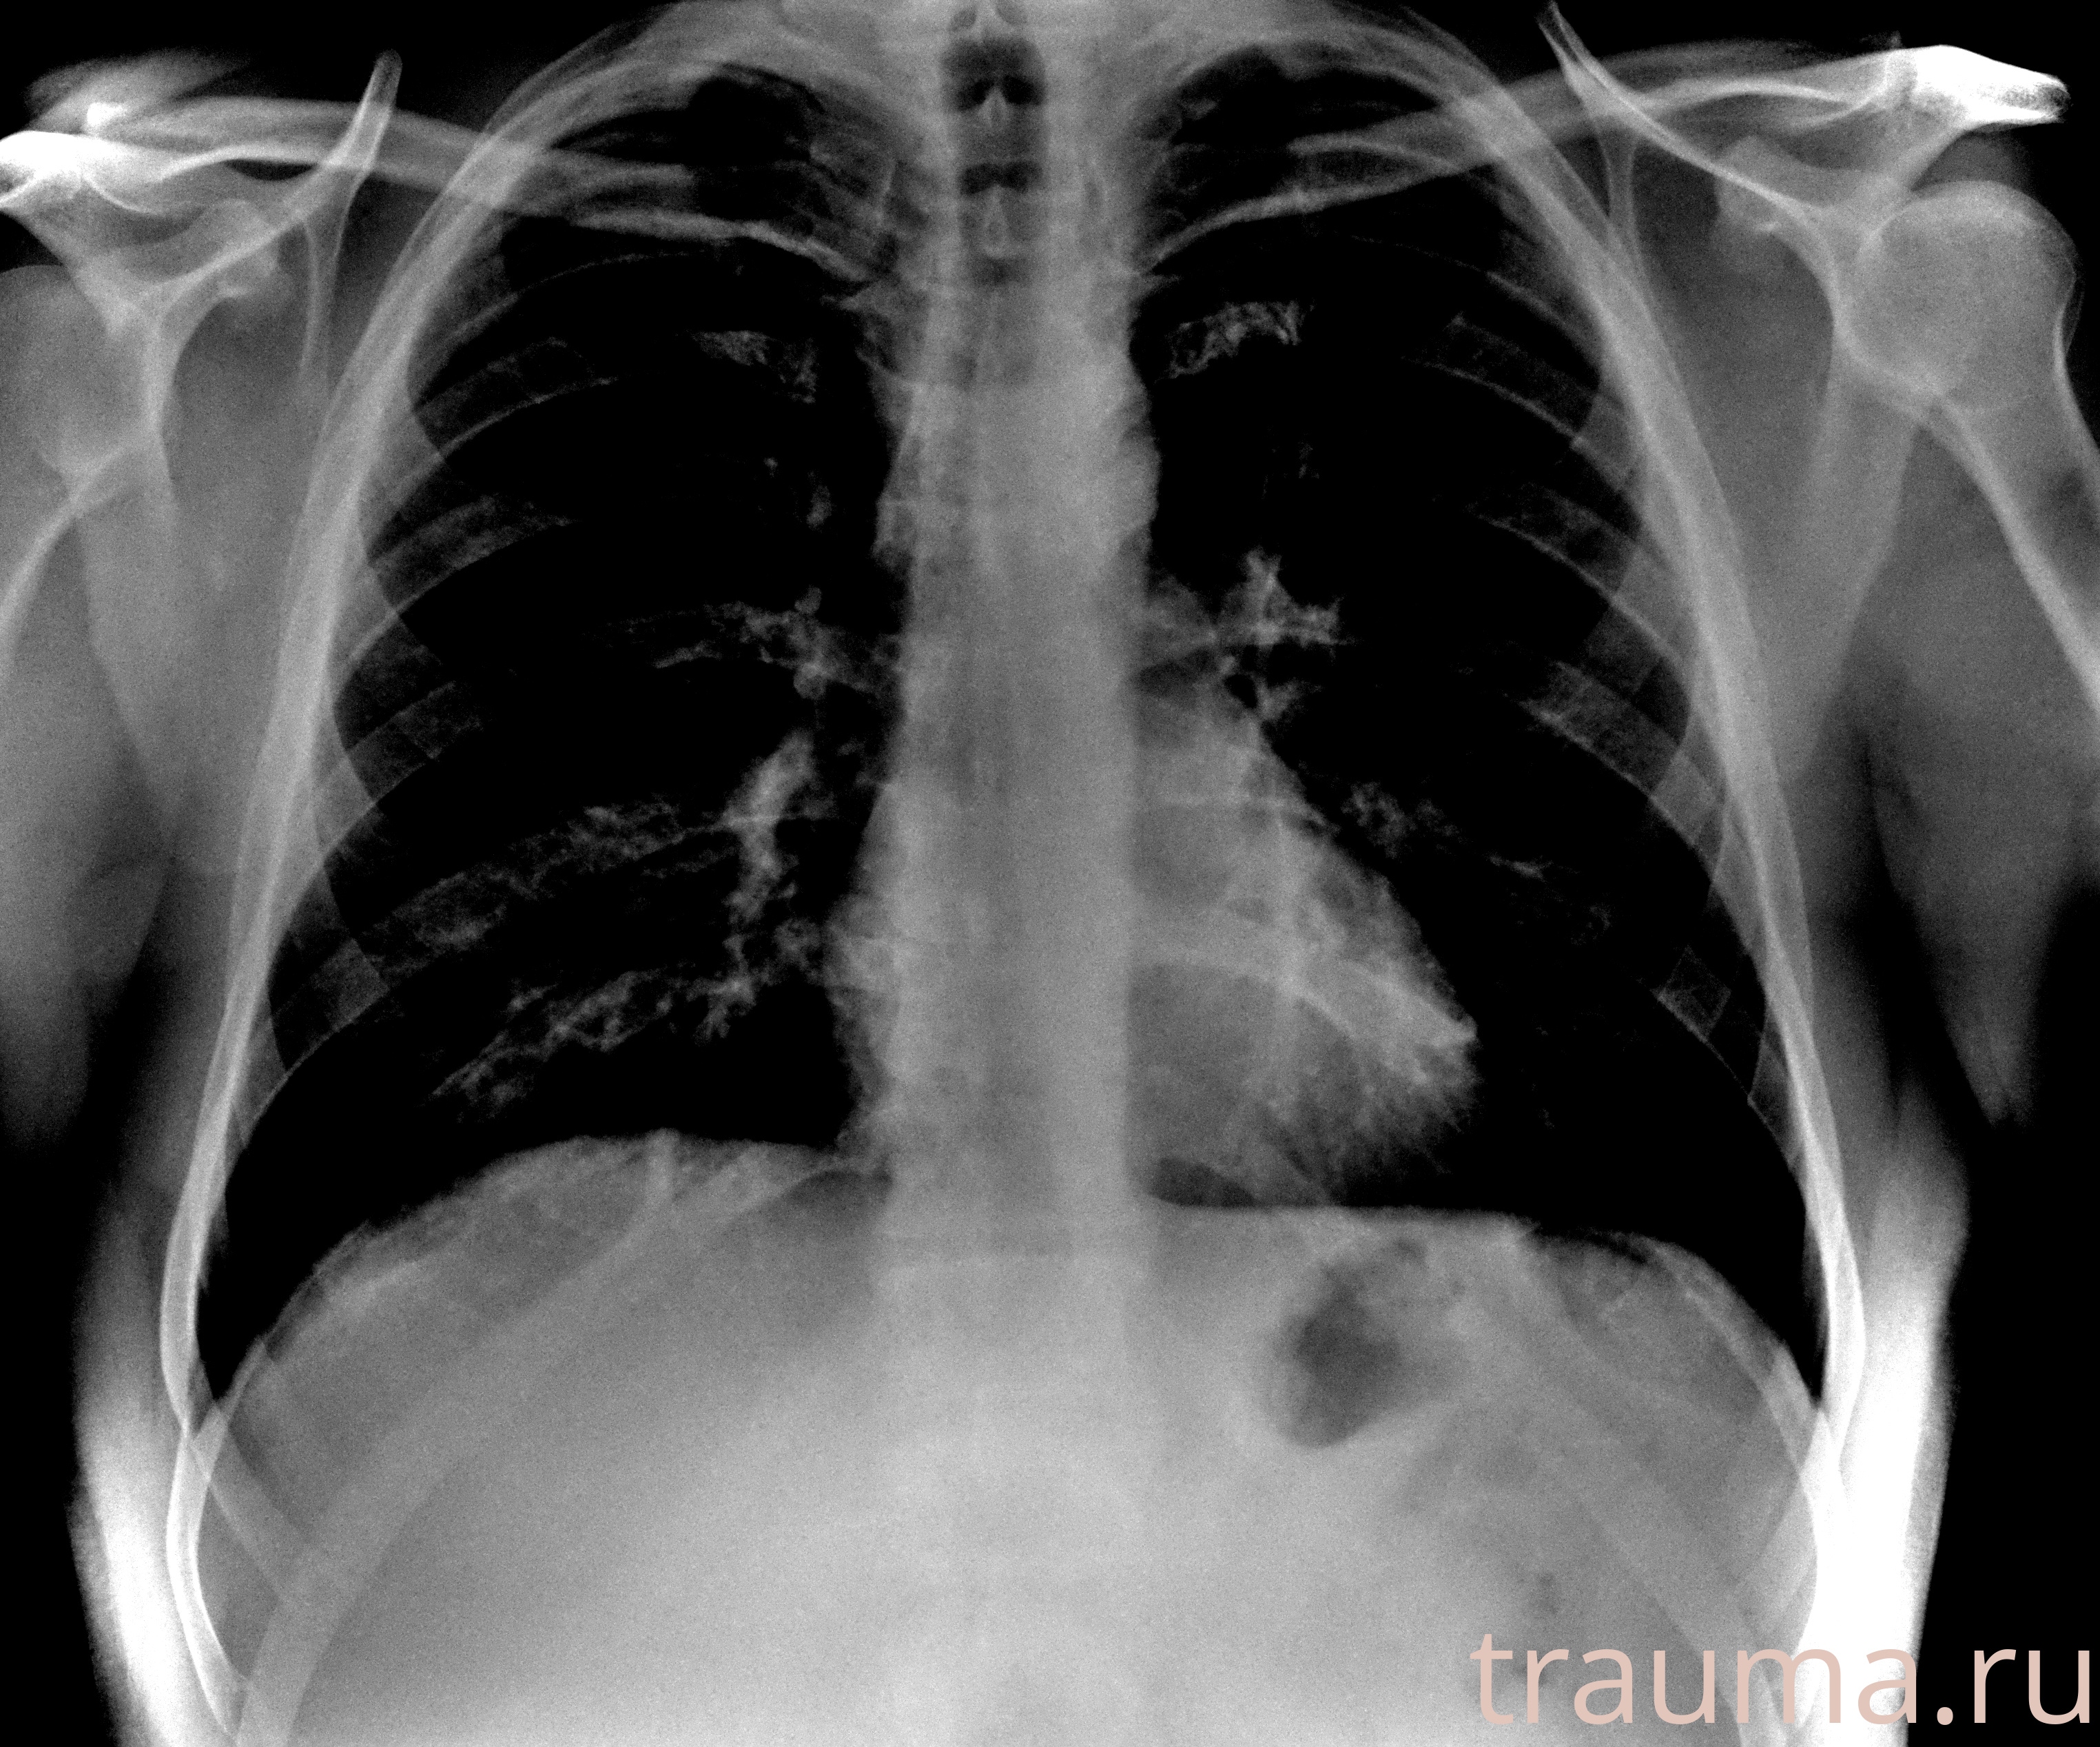

Рентген на дому: по вашему адресу приезжает врач-рентгенолог, травматолог-ортопед с мобильным рентгеновским аппаратом, проводит диагностику травмы или заболевания, делает необходимые рентгенограммы, дает рекомендации по дальнейшему лечению. Получить качественные снимки в домашних условиях возможно благодаря уникальной методике, разработанной МосРентген Центром для института  Склифосовского